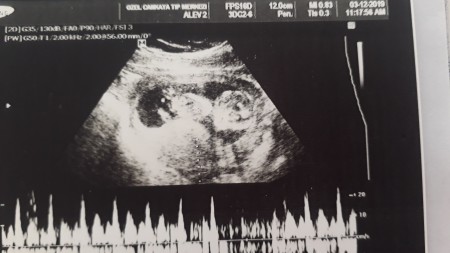

Cinsiyetini merak ediyorum acaba resimde ne görüyosunuz doktorum haftaya gel dedi

Gebelik haftası 12 hafta 5 gün

Cıkıntı yok gbi kıza benziyo Benimde bu bak erkek ;))

Bacaklarınin arasinda cıkıntı oldumu erkek olmadimi kiz oluyo

Ben bakar bakmaz erkek gibi hissettim canım

Kız bu kız cok kibar duruyo :D

12.haftada erken belirginleşmiş vücudu. Erkeklerde öyle oluyormuş genelde.